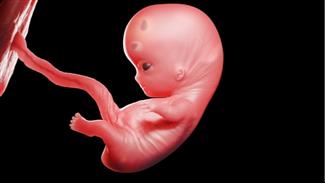

מאת: מערכת אינפומד 20/02/2019הוא אמנם עדיין קטנטן, אבל המוח, הלב, עמוד השדרה והשרירים של העובר שלך מתחילים להתפתח. ומה עובר עליך? לפניך כתבה על ... לכתבה המלאה